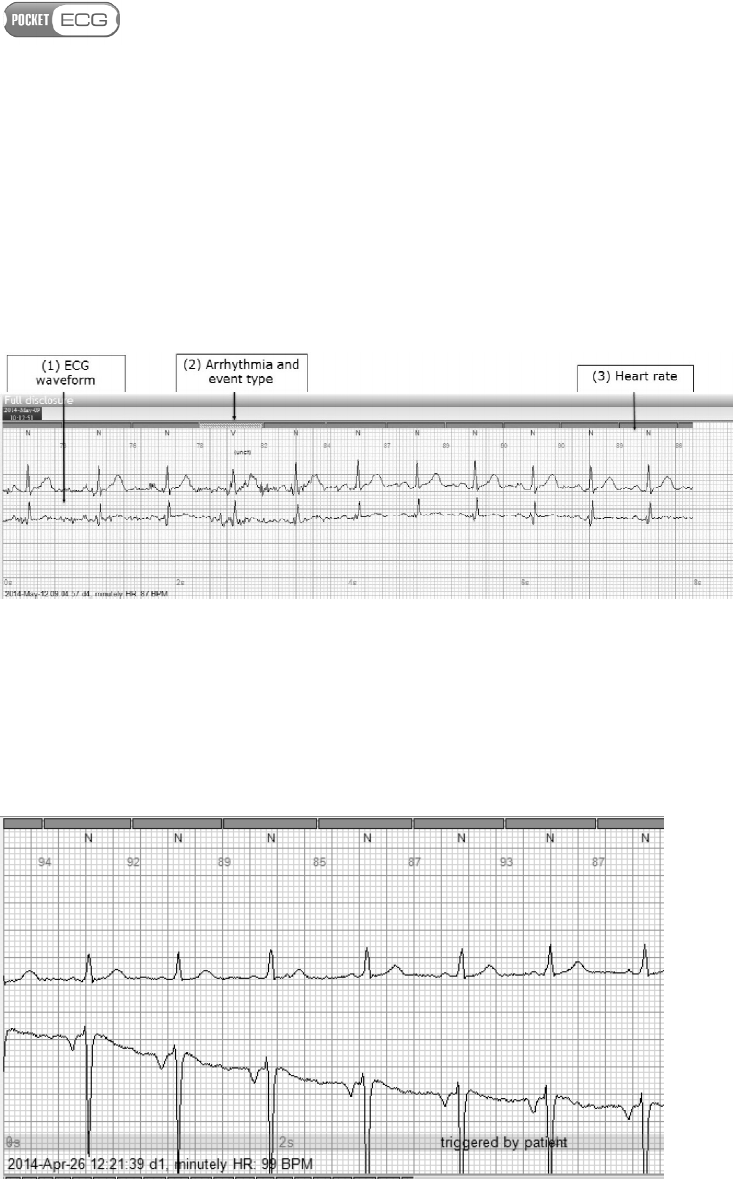

The PocketECG PC Client provides access to full disclosure ECG

Disclosure view of the PC client application, as shown in Fig. 25.

Fig. 25 Full Disclosure view

The timeline bar is displayed in the upper part of the screen. The user

may click on the timeline bar in order to navigate directly to any time

in the recording. The ECG waveform is displayed in normal size - as 8 s

strip in the upper part of the screen and as a miniaturized signal in the

bottom part of the screen (30 s of the signal in each row). User may

click on the miniaturized ECG and the corresponding full size strip will

be displayed in the upper part of the screen. The displayed strip is

Page 88 of 118

indicated by yellow frame highlighting the corresponding miniaturized

ECG fragment. The enlarged fragment of the Full Disclosure view

containing the ECG strip is presented in Fig. 26. The PocketECG

automatically detects and classifies QRS complexes. The annotations

for all detected complexes are displayed above the ECG beats (2). The

instantaneous heart rate is displayed between the ECG beat labels (3).

Fig. 26 ECG waveforms presented in the upper part of the screen

The PocketECG transmitter allows the patient to report symptoms

manually. The ECG strip reported (marked) by the patient is presented

in the Full Disclosure view with a long grey stripe marked with

"triggered by patient" label located under the ECG waveform (Fig. 27)

Page 89 of 118

Fig. 27 ECG waveforms marked as "triggered by patient"